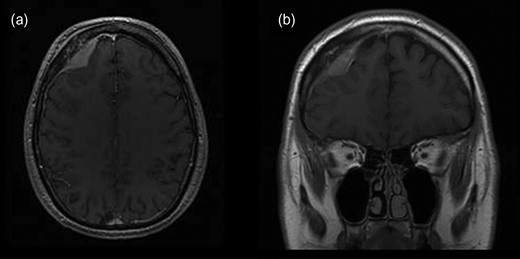

The patient was transferred to the hematology department for further diagnostic procedures. Upon analysis no pathological findings were found. After consultation R-CHOP and intrathecal methotrexate protocol was chosen. The patient was administered four cycles of R-CHOP and intrathecal methotrexate. Four months afterwards, MRI and neurosurgical control were performed. MRI revealed satisfying postoperative result without any new intracranial masses (Fig. 3).

MRI scans of brain, 4 months postoperatively, revealing no recurrence of lymphoma in (a) transverse and (b) coronal plain.